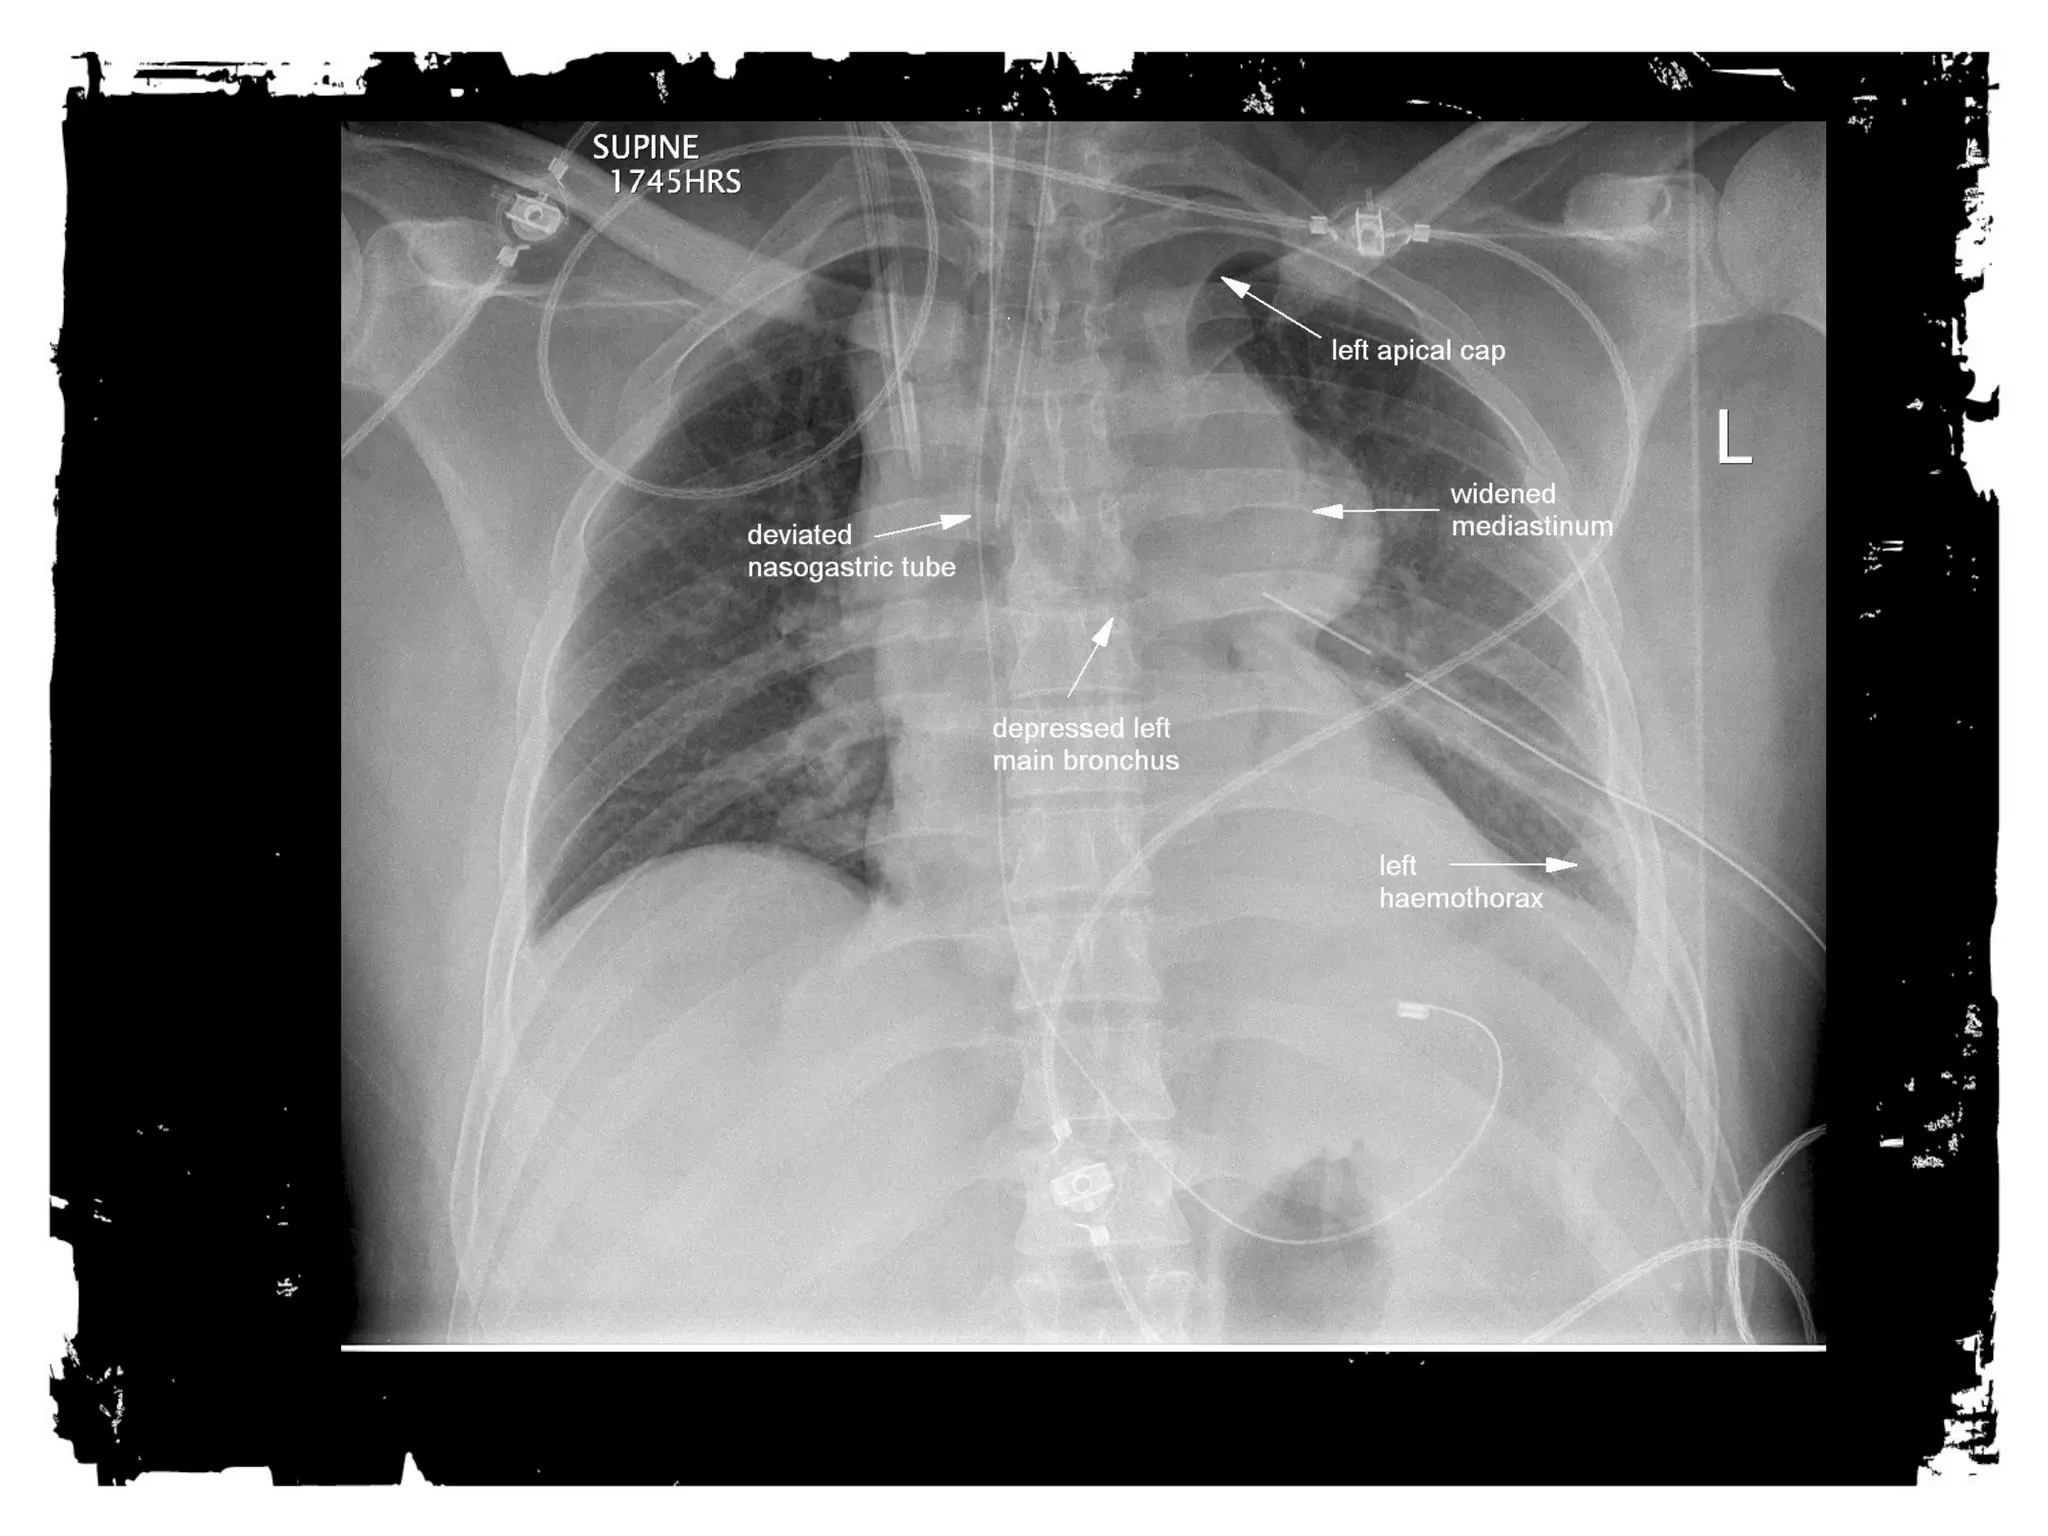

HEMOTHORAX

• Venous or arterial bleeding

• 60% controlled by chest tube,

40% need operative

management

• Can miss hundreds of cc’s on

supine film

• Can be tension

Traumatic aortic rupture

After chest trauma, imaging plays a key role for both,

the primary diagnostic work-up, and the secondary

assessment of potential treatment. Despite its well-known

limitations, the AP chest radiograph remains

the starting point of the imaging work-up. Adjunctive

imaging with CT, that recently is increasingly often

performed on MDCT units, adds essential

information not readily available on the CXR. This

allows better definition of trauma-associated thoracic

injuries not only in acute traumatic aortic injury, but

also in pulmonary, tracheobronchial, cardiac,

diaphragmal, and thoracic skeletal injuries.